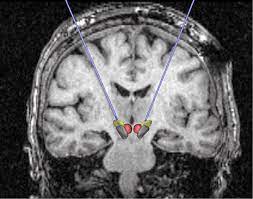

Au global, 143 patients (âge moyen 47,4 ans, dont 98 femmes) ont été inclus dans les analyses. En moyenne, les examens par PET scans ont été réalisés 10,9 mois après apparition des premiers symptômes. Sur la base de l’interprétation visuelle de médecins expérimentés, 53% des scans ont été interprétés comme normaux, 21% comme légèrement à modérément affectés et 26% comme sévèrement affectés, ce qui correspondait respectivement à aucune atteinte, une atteinte incomplète ou légère à modérée ou une atteinte sévère des bulbes olfactifs de la région fronto-basale et des régions cérébrales connectées (y compris les régions limbiques/paralimbiques, le tronc cérébral et le cervelet).